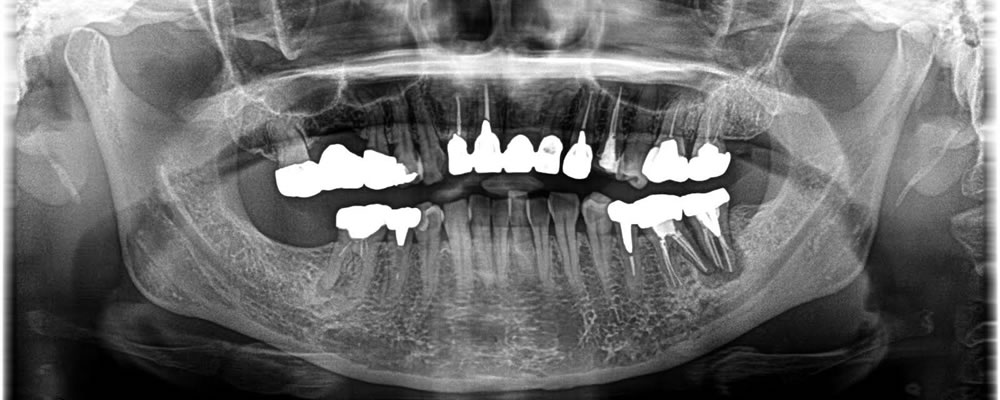

こちらの患者さまは、奥歯の痛みが強く残す事ができないと他院にて診断され、インプラント治療希望で当院へお越し頂きました。

一番奥の歯だけではなく手前の歯にも感染が拡がっていたため、2本の歯を抜歯後にインプラント1本を埋入し、骨が無くなってしまっている部分に骨を作る処置を一度のオペで行いました。